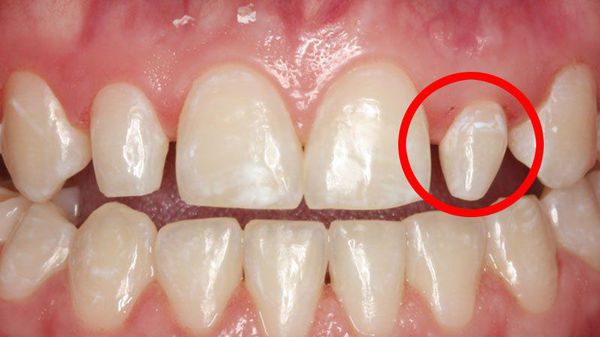

Ewaginacja zęba (evaginatio dentis) to anomalia rozwojowa dotycząca korony zęba, powstająca w trakcie formowania się zawiązków zębów. Objawia się obecnością dodatkowego guzka (wypukłości) na powierzchni korony, zbudowanego ze szkliwa (enamelum) i zębiny (dentinum). Guzek ten może mieć różny rozmiar, kształt oraz umiejscowienie – od niewielkiego zgrubienia po wyraźną strukturę w kształcie rogu, stożka lub piramidy.

W literaturze medycznej ewaginacja zęba występuje również pod innymi nazwami: guzkowate uwypuklenie, guzek pazurowaty (claw cusp), przedtrzonowiec Leonga (zęby Leonga) lub perła szkliwna okluzyjna (perła szkliwna okluzyjna). Anomalia ta może dotyczyć zarówno zębów mlecznych, jak i stałych, najczęściej przedtrzonowców, i może prowadzić do problemów funkcjonalnych – m.in. nadmiernego kontaktu z zębami przeciwstawnymi czy zwiększonego ryzyka pęknięcia szkliwa.

Evaginacja zęba

Inwaginacja zęba (dens invaginatus) i ewaginacja zęba (evaginatio dentis) nie tylko pogarszają estetykę, ale też zwiększają ryzyko gromadzenia się płytki nazębnej i resztek pokarmowych, co sprzyja rozwojowi próchnicy (caries dentium). Dodatkowo ewaginacja może powodować urazy języka podczas żucia lub mówienia. W niektórych przypadkach prowadzi także do bólu w obrębie stawu skroniowo-żuchwowego (staw skroniowo-żuchwowy, TMJ) z powodu nadmiernego nacisku i przeciążenia wystającego guzka.

Ewagynacja zęba (ewaginacja szkliwa, dental evagination) to anomalia, w której na powierzchni korony zęba pojawia się dodatkowy guzek zbudowany z twardych tkanek – szkliwa (enamelum) i zębiny (dentinum). Choć początkowo może nie powodować dolegliwości, z czasem prowadzi do powikłań wynikających z przeciążenia mechanicznego i zwiększonego ryzyka uszkodzeń.

Najczęstsze następstwa to:

• Martwica miazgi (necrosis pulpae) – obumarcie tkanek wewnątrz zęba w wyniku urazu lub starcia guzka, przez co bakterie mogą dostać się do wnętrza zęba;

• Zakażenie okołowierzchołkowe (infectio periapicalis) – infekcja w obrębie tkanek otaczających wierzchołek korzenia, która może prowadzić do zapalenia kości lub utraty zęba;

• Przeciążenie okluzyjne (overload occlusalis) – dodatkowy guzek zaburza prawidłowe zwarcie (okluzję), przez co siły żucia rozkładają się nierównomiernie;

• Ból w obrębie dziąseł lub stawu skroniowo-żuchwowego (articulatio temporomandibularis) – wynikający z długotrwałego napięcia mięśni żucia i nieprawidłowego kontaktu zębów.

W przypadku ewagynacji w zębach przednich guzek może sięgać aż do krawędzi siecznej, co powoduje dyskomfort estetyczny, utrudnia wymowę i zwiększa ryzyko urazu mechanicznego. Wczesne rozpoznanie jest istotne, ponieważ profilaktyczne zeszlifowanie lub zabezpieczenie guzka materiałem kompozytowym może zapobiec pęknięciu i martwicy miazgi.

Evaginacja górnego siekacza

Ewagynacja zęba (ewaginacja szkliwa i zębiny, dental evagination) jest natomiast widoczna klinicznie – w postaci dodatkowego guzka lub wypukłości na powierzchni korony. Mimo że można ją rozpoznać gołym okiem, wykonanie radiogramu jest niezbędne, aby wykluczyć współistniejące anomalie, takie jak inwaginacja zęba (dental invagination) czy zęby nadliczbowe (dentes supernumerarii). Na zdjęciu rentgenowskim ewagynacja ma strukturę typową dla prawidłowych tkanek twardych – składa się z szkliwa (enamelum) i zębiny (dentinum), co potwierdza jej pochodzenie rozwojowe, a nie patologiczne.